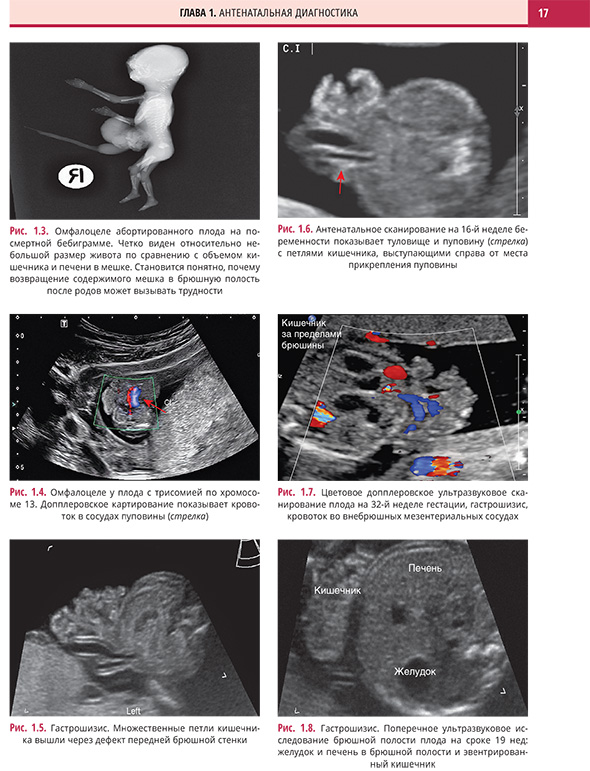

Дефекты передней брюшной стенки